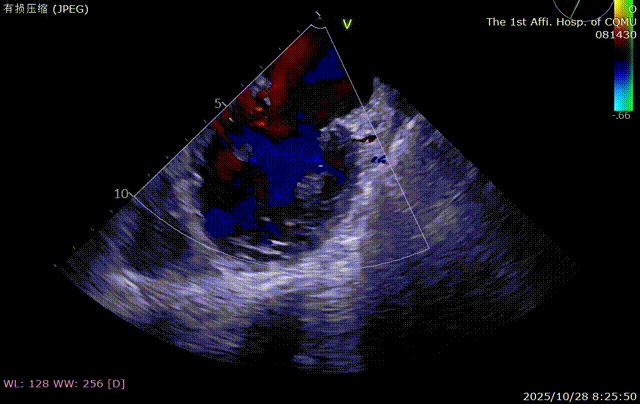

术后复查经胸心脏超声,示肺静脉、肝静脉逆流消失,二尖瓣及三尖瓣反流降低至轻度,手术效果良好。

术后恢复情况